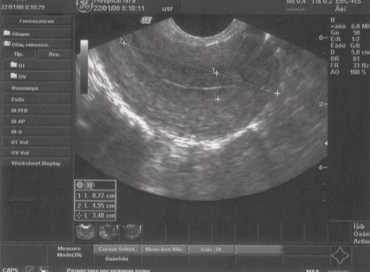

Номальные яичники

Рис. 2. Нормальный яичник с фолликулряным аппаратом.

Доминантного фолликула нет, поскольку исследование проводилось на 3 день менструального цикла.

При оценке состояния яичников по УЗИ определяется:

- Положение яичников.

В норме расположены по бокам от матки, чаще всего несимметрично, на небольшом расстоянии от углов матки. Форма яичников, как правило, овальная, при этом правый и левый яичники совершенно не идентичны друг другу. - Размеры яичников (продольный, передне-задний и поперечный).

Средние значения размеров нормальных яичников в длину от 2,4 до 4,0 см, переднее-заднего от 1,5 до 2,5 мм. - Структура яичников.

В норме яичники состоят из капсулы и фолликулов различной степени зрелости (в первой фазе цикла). Во второй фазе цикла, как правило, визуализируется желтое тело - признак произошедшей овуляции. Число фолликулов может быть неодинаковым слева и справа. Зреющий фолликул выявляется уже в первой фазе цикла и достигает к овуляции максимальных размеров, в среднем около 20 мм.

Содержимое доминантного фолликула однородное, поскольку он содержит фолликулярную жидкость, а капсула тонкая. После овуляции на месте доминантного фолликула образуется желтое тело, которое имеет, как правило, сетчатую эхоструктуру (оно содержит жировую ткань) и также тонкую капсулу - 1-2 мм. Чаще всего по форме это образование овальное или неправильно формы.